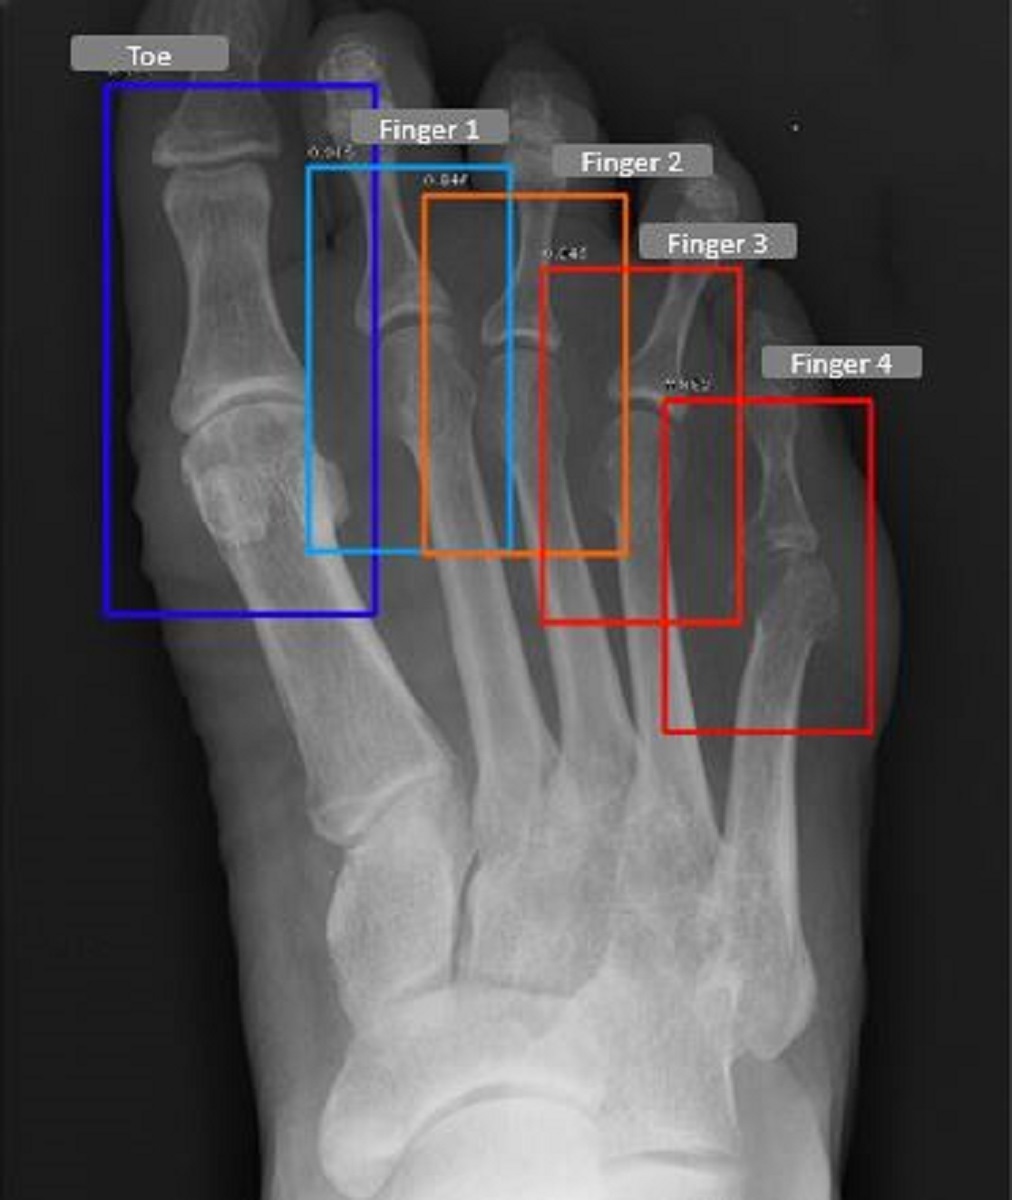

Refer to caption

(b) Feet Fingers/Toe detected by the model

Figure 3: Fingers, wrists and thumb/toe identified by the detection models for a patient

We evaluate the detector models on the test dataset which comprised of 50 Hands/Feet radiographs respectively, these radiographs were not used during the training and validation. The detector model, for the feet was able to achieve a mAP of 0.965, whereas the hand model achieved a mAP of 0.981 at an intersection over union threshold (IOU) of 0.6. In Table 1, we report the joint wise average precision (AP), we observe that the wrist joint being the easiest to detect, achieves the highest AP, whereas all other joints have a relatively similar AP in the case of both detector models. Fig. 4 represents the joints detected for a patient in the test set.

Thumb/Toe 0.986 0.983

Finger 1 0.979 0.973

Finger 2 0.983 0.955

Finger 3 0.971 0.947

Finger 4 0.977 0.965

Wrist 0.993 -

Overall mAP 0.981 0.965